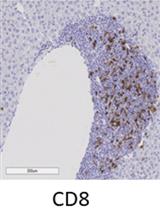

Immune cell infiltration, particularly cytotoxic CD8α lymphocyte infiltration, plays an important role in development of diabetic nephropathy. Although CD8α infiltration can be evaluated by its production of cytokines, its localization in the kidney is of particular importance. The current protocol describes CD8α immunostaining using a Vectastain ABC kit. This protocol works well with most commercially available antibodies, including CD8α antibodies in kidneys of diabetic mice.

Diabetic nephropathy (DN), a complication of diabetes, is the most common cause of end-stage renal disease. Pathological changes in DN are closely correlated with the degree of renal immune cell infiltration, particularly toxic CD8α lymphocyte infiltration. Therefore, a sensitive and reliable method to localize CD8α lymphocytes in the kidney will facilitate the research in diabetic nephropathy as well as other fields relating inflammation (Li et al., 2018).

Zhang, M. and Harris, R. C. (2019). Immunohistochemical Staining of CD8α in Diabetic Mouse Kidney. Bio-protocol 9(18): e3364. DOI: 10.21769/BioProtoc.3364.